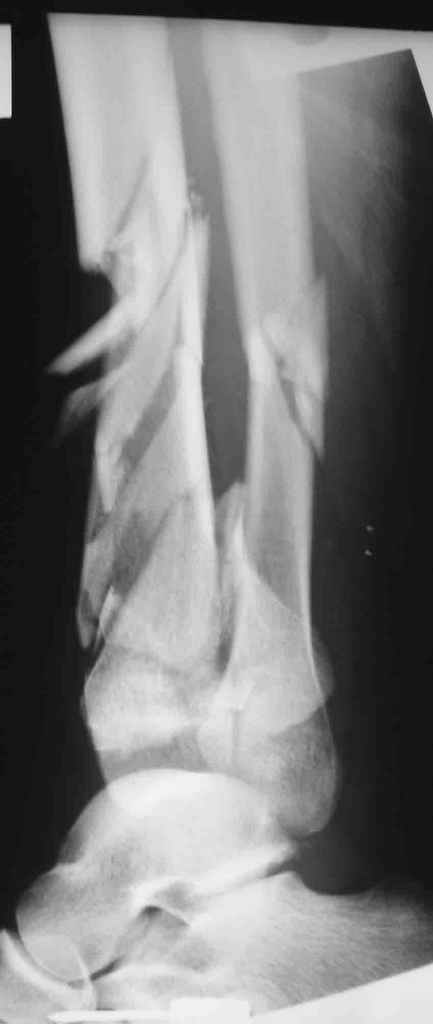

В качестве альтернативы - ограниченная, минимально инвазивная открытая репозиция суставного конца кости, фиксация спицами и винтами; продолжние аппаратной фиксации, уже со свободной стопой - месяца 2-3. После сращения дистального "блока" - закрытый интрамедуллярный остеосинтез.

Возможный альтернативный способ : накостный остеосинтез м/берцовой кости, открытый чрескостный остеосинтез эпиметафиза б/берцовой кости.

на мой взгляд не стоило менять шило на мыло. Для подбных случаев как раз наиболее подящий вариант внеочаговая фиксация.Темолее что стояние отломков удовлетворительное. в крайнем случае при дисконгруэнности сусавных поверхностей открытая репозиция и трансартикульрная фиксация в аппарате.